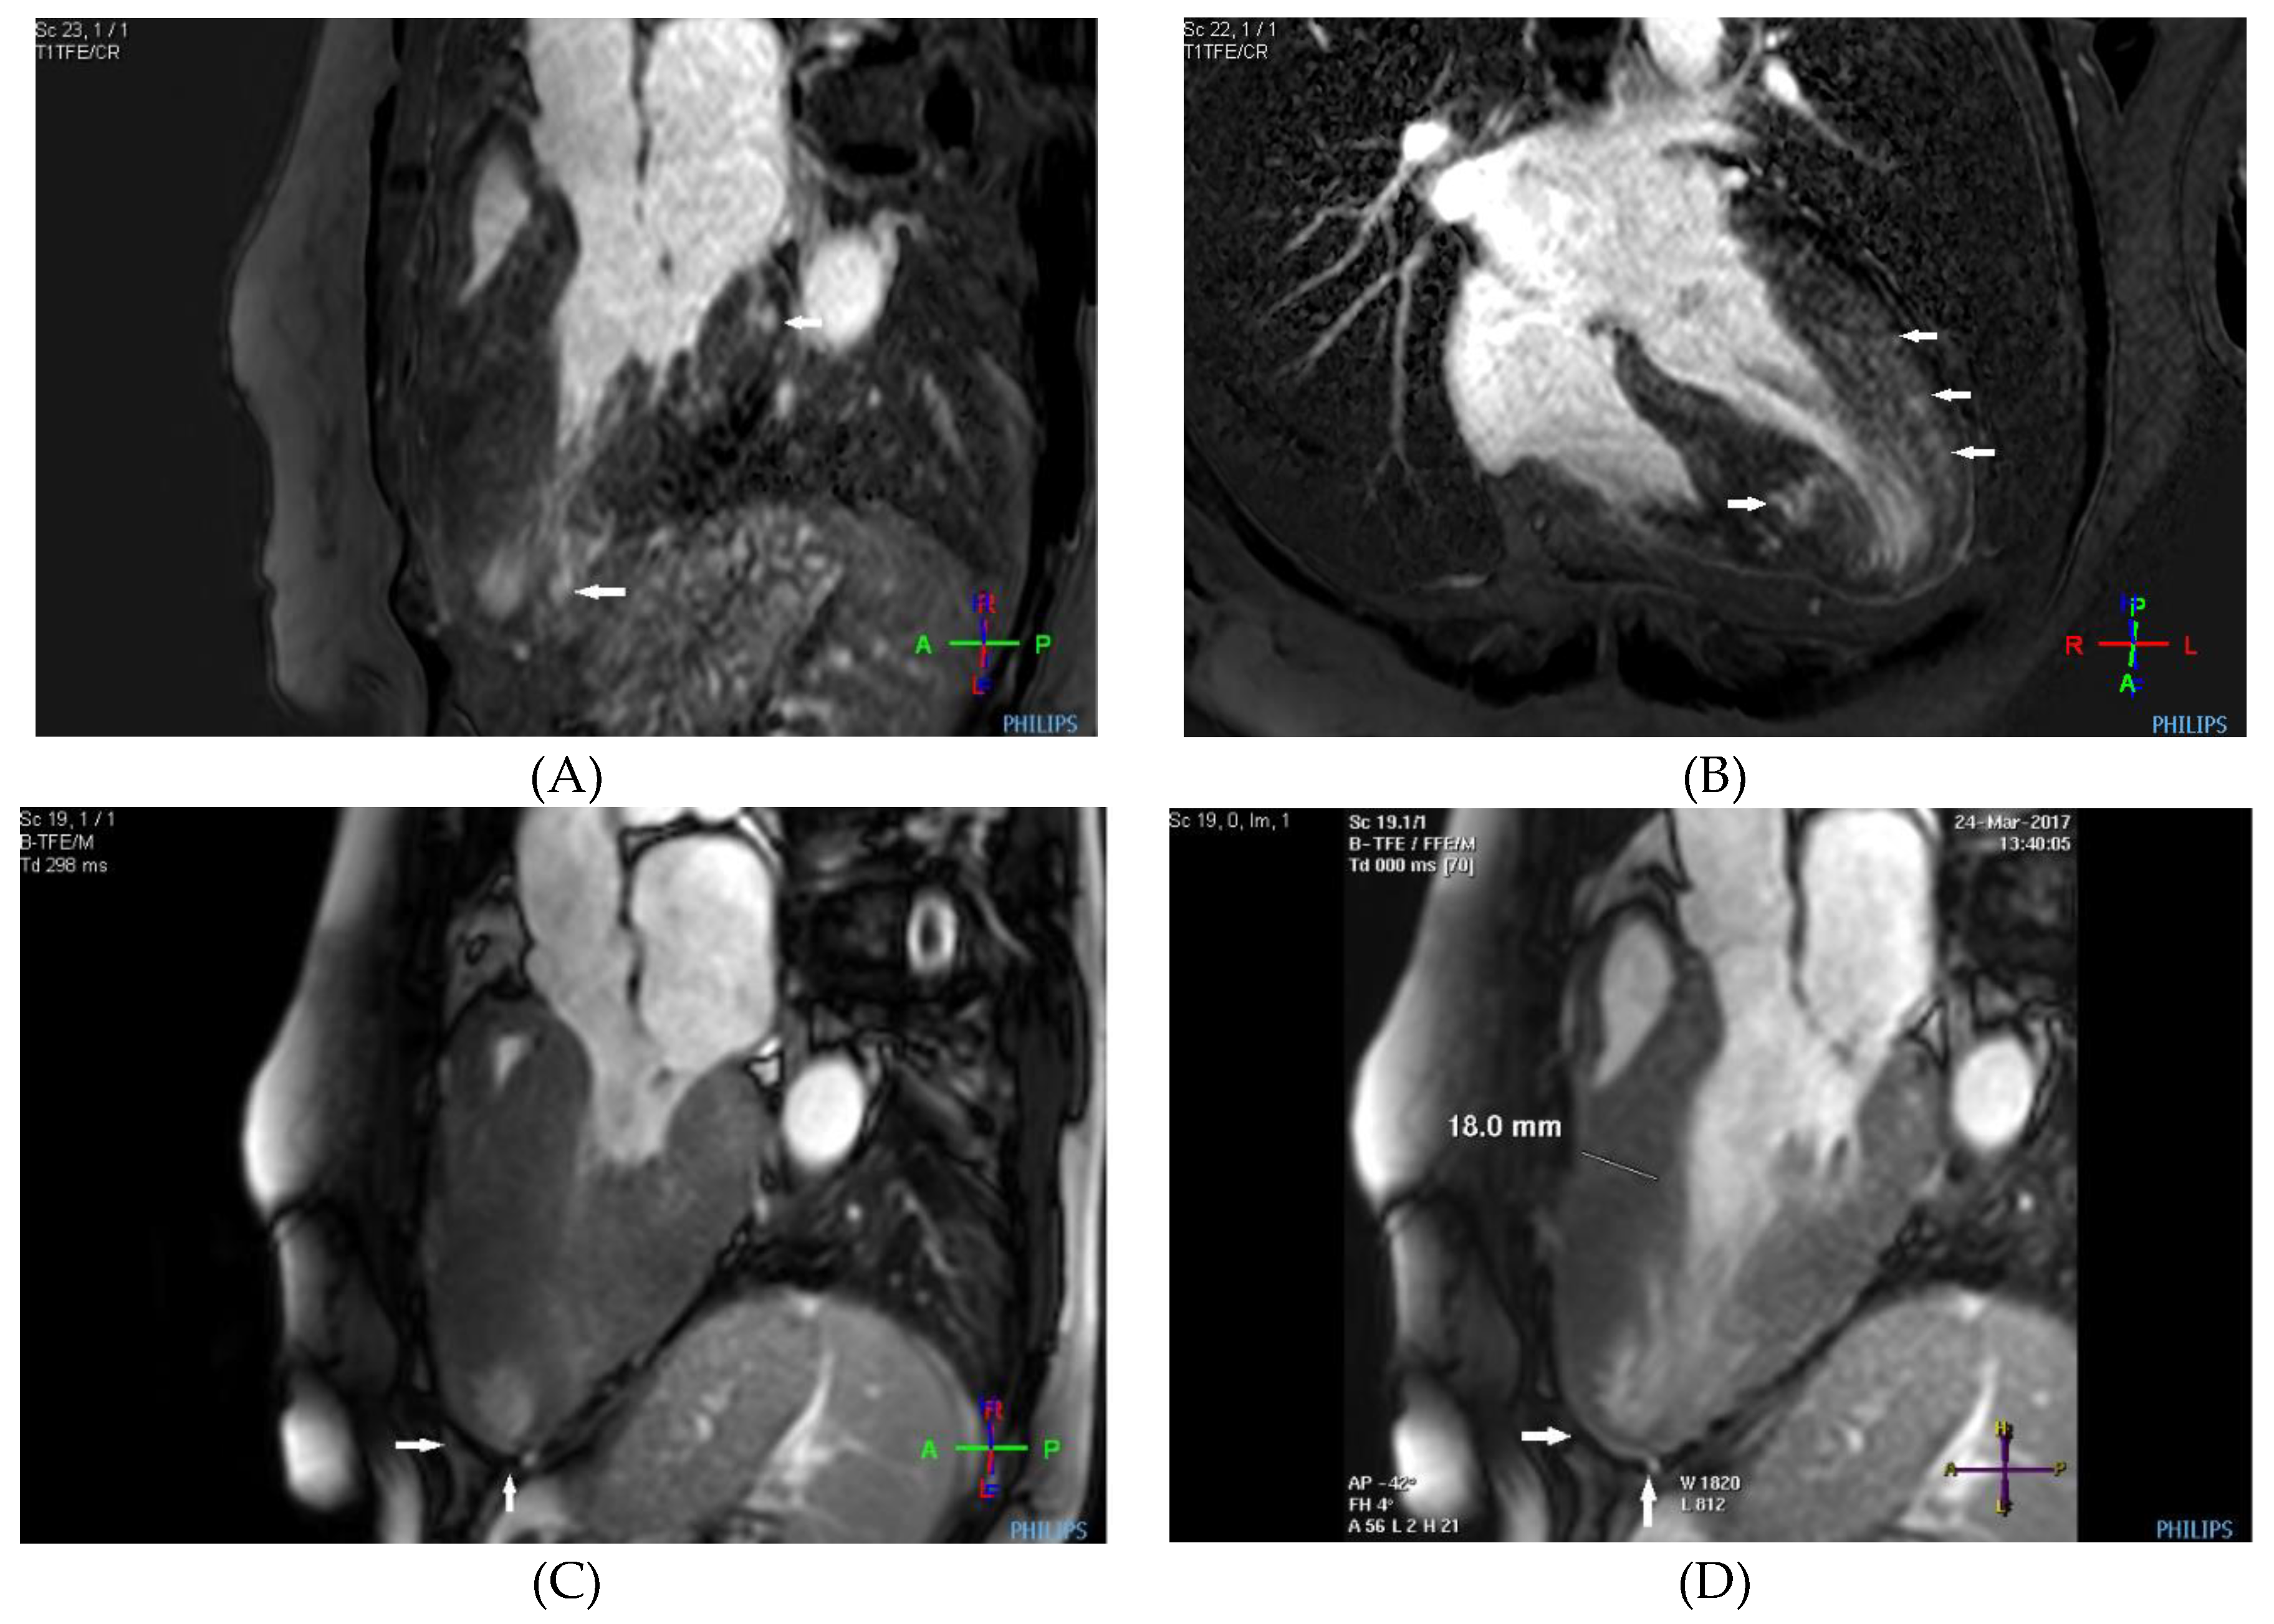

Case description